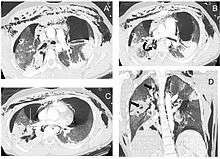

| Reconstruction of the trachea and bronchi with x-ray computed tomography showing disruption of the right main bronchus with abnormal lucency (arrow)[1] | |

Chest x-ray is the initial imaging technique used to diagnose TBI.[9] The film may not have any signs in an otherwise asymptomatic patient.[13] Indications of TBI seen on radiographs include deformity in the trachea or a defect in the tracheal wall.[9] Radiography may also show cervical emphysema, air in the tissues of the neck.[2] X-rays may also show accompanying injuries and signs such as fractures and subcutaneous emphysema.[2] If subcutaneous emphysema occurs and the hyoid bone appears in an X-ray to be sitting unusually high in the throat, it may be an indication that the trachea has been severed.[4] TBI is also suspected if an endotracheal tube appears in an X-ray to be out of place, or if its cuff appears to be more full than normal or to protrude through a tear in the airway.[9] If a bronchus is torn all the way around, the lung may collapse outward toward the chest wall (rather than inward, as it usually does in pneumothorax) because it loses the attachment to the bronchus which normally holds it toward the center.[6] In a person lying face-up, the lung collapses toward the diaphragm and the back.[10] This sign, described in 1969, is called fallen lung sign and is pathognomonic of TBI (that is, it is diagnostic for TBI because it does not occur in other conditions); however it occurs only rarely.[6] In as many as one in five cases, people with blunt trauma and TBI have no signs of the injury on chest X-ray.[10] CT scanning detects over 90% of TBI resulting from blunt trauma,[3] but neither X-ray nor CT are a replacement for bronchoscopy.[6]